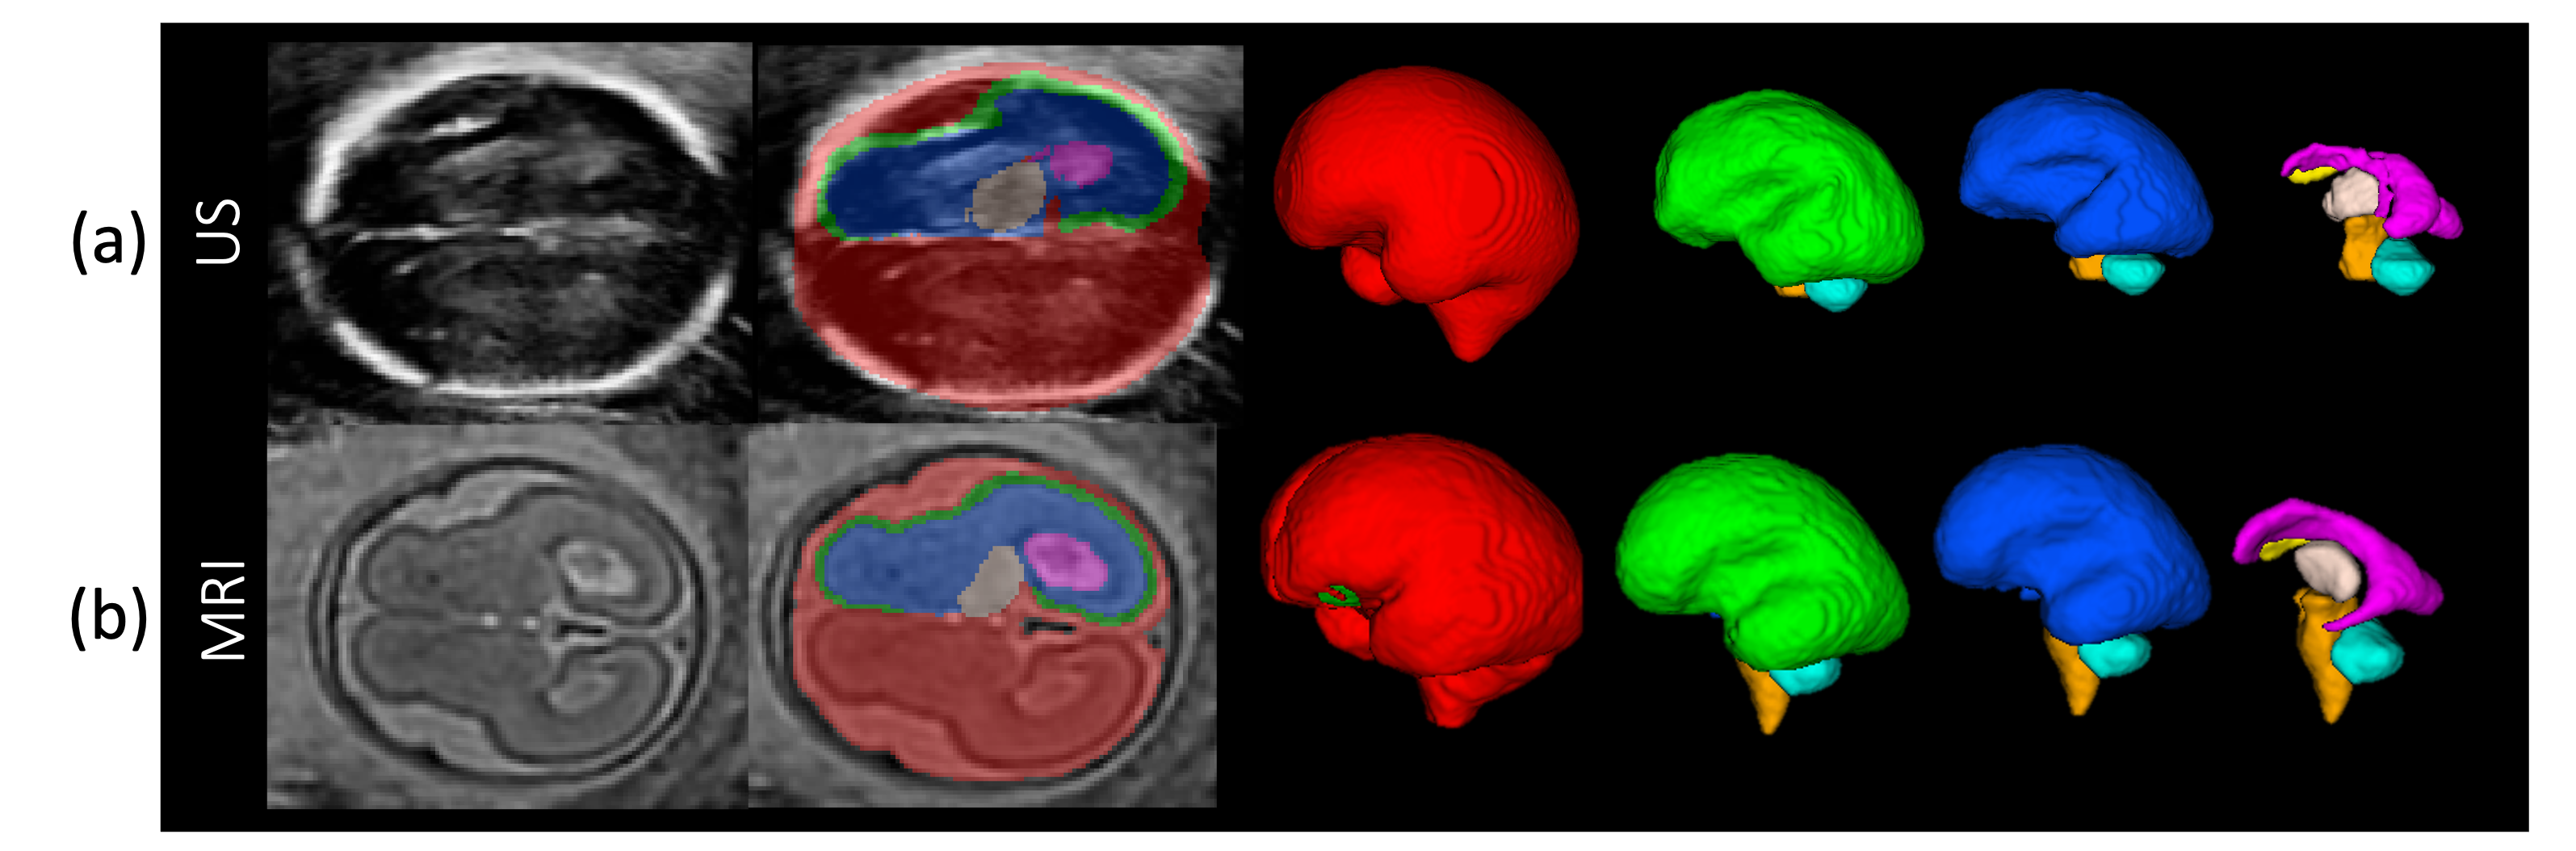

Cross‐Modality Comparison of Fetal Brain Phenotypes: Insights From Short‐Interval Second‐Trimester MRI and Ultrasound Imaging

Human Brain Mapping

·

01 Oct 2025

·

doi:10.1002/hbm.70349

Subcortical segmentation of the fetal brain in 3D ultrasound using deep learning

NeuroImage

·

01 Jul 2022

·

doi:10.1016/j.neuroimage.2022.119117